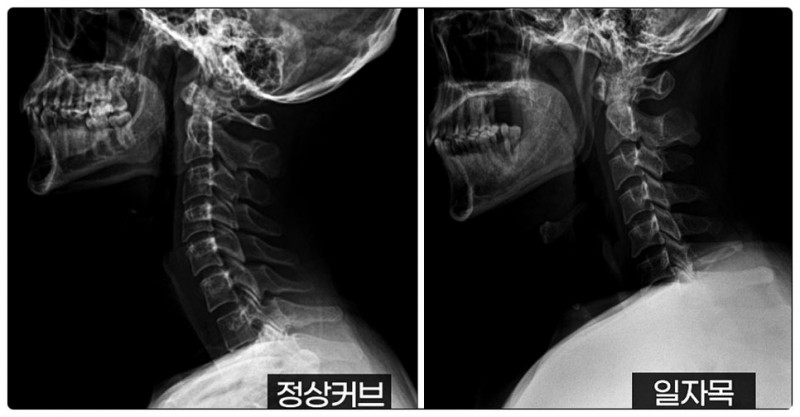

경추, 즉 목뼈는 원래 완만한 C자 곡선을 가지고 있습니다.

이 곡선은 자동차 서스펜션처럼 충격을 흡수하는 역할을 하지요.

그런데 교정이 필요한 경우, 이 곡선이 사라지면서 충격 완화 능력이 떨어집니다.